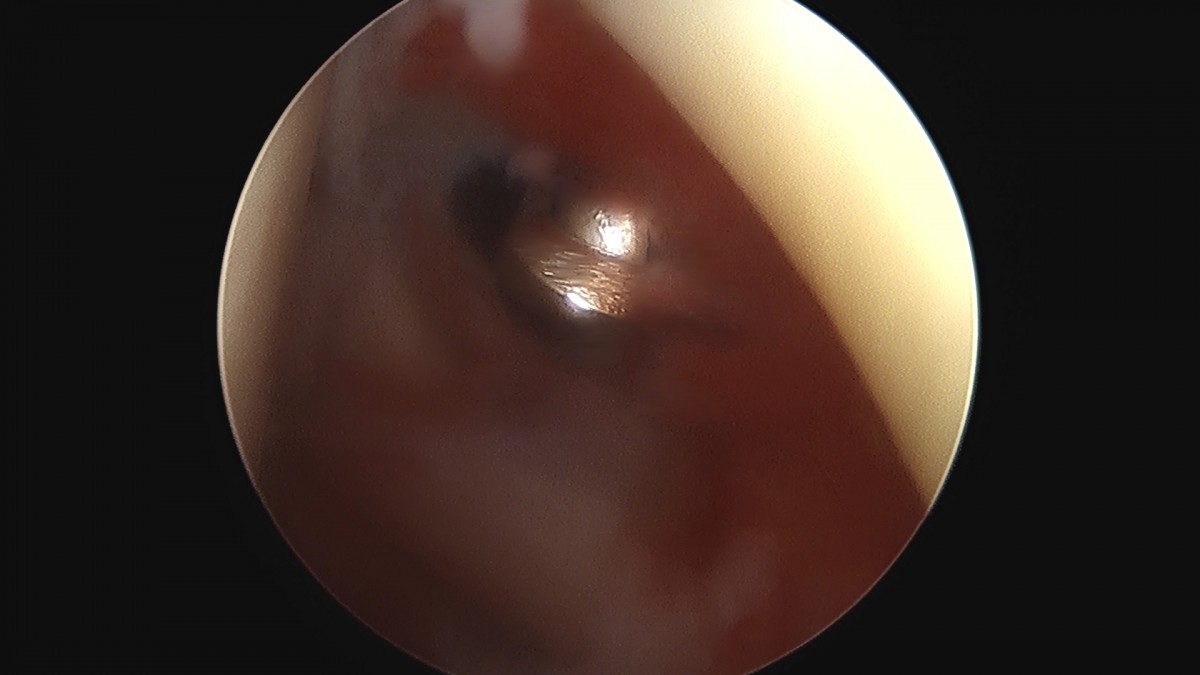

이재상원장님 어깨 견봉하 감압술 김봉O 환자

작성자 최고관리자 댓글 0건 조회 811회 작성일 25-09-16 15:28